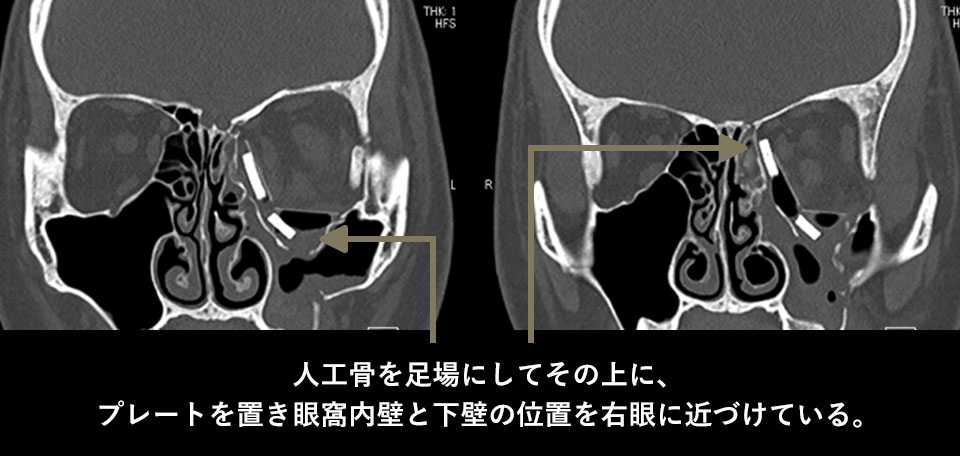

手術は白目(結膜)の切開から行ったため、皮膚に傷は残っていません。人工骨で足場を作り、その上にプレートが乗せました。

術後のCTを見ると眼窩の断面積が正常である右に近づいているのが分かります。